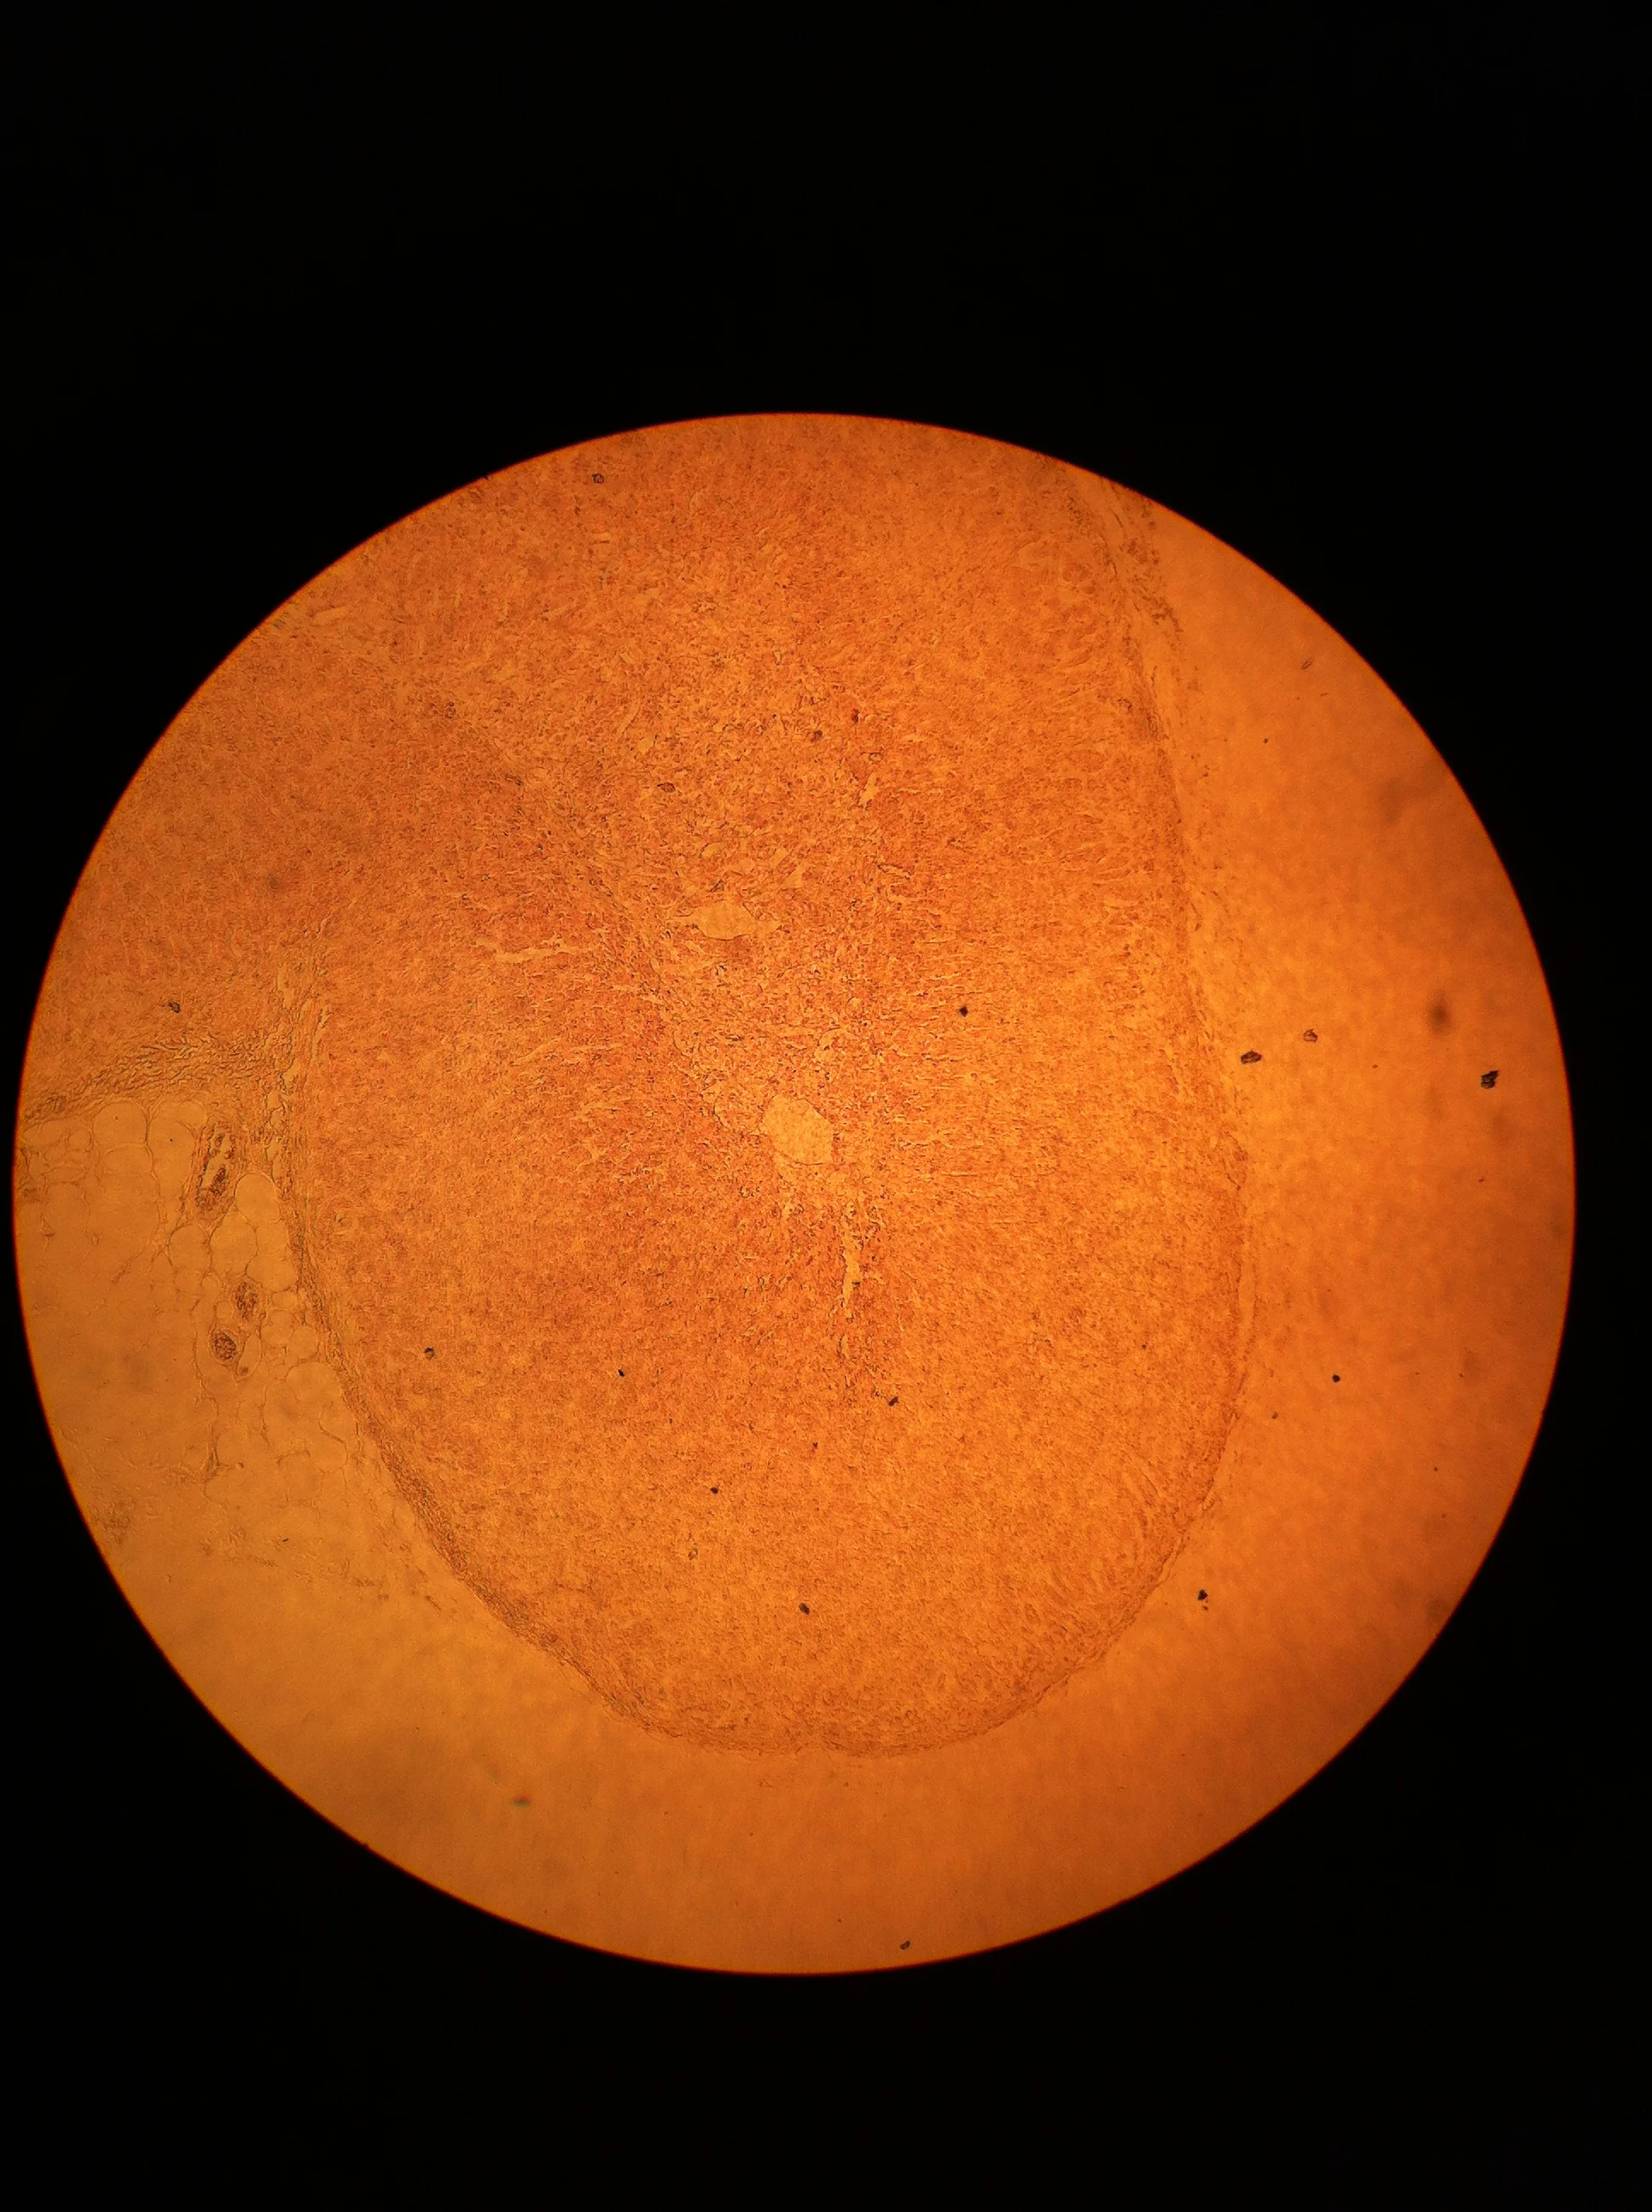

Pancreatic Islet 100X

Pancreatic Islet 400X